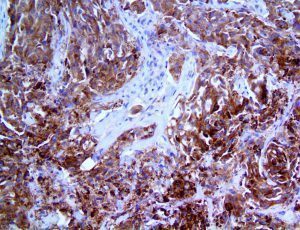

It is the ICU physician who is most likely to witness one of the deadliest manifestations of the abnormal immunological response, the cytokine storm syndrome (CSS). This response is also referred to by some as the cytokine release syndrome (CRS). CSS is characterized by continuous activation and expansion of macrophage and lymphocyte populations, which secrete large amounts of cytokines, causing the cytokine storm. This massive cytokine release is akin to hemophagocytic lymphohistiocytosis (HLH) disease, a syndrome characterized by initial unchecked and persistent activation of cytotoxic T lymphocytes and NK cells.

Clinical and laboratory manifestations of HLH include fever, enlarged liver and/or spleen, neurologic dysfunction, coagulopathy, liver dysfunction, cytopenias (i.e., low levels of erythrocytes, leukocytes, and/or platelets), hypertriglyceridemia, hyperferritinemia, hemophagocytosis, and eventually diminished NK cell activity as the immune system becomes progressively paralyzed. HLH can be familial (primary HLH) or secondary to another disease process (sHLH), such as rheumatic disease, in which it is referred to as macrophage activation syndrome (MAS, characterized by elevated ferritin).

This activation induces inflammatory monocytes to highly express IL-6, starting a localized and then systemic cascade effect that results in hyperproduction of IL-6, which accelerates the inflammatory process. Because IL-6 also increases vascular permeability, excessive levels cause blood vessels to become very leaky. This, along with clotting factors released from vascular endothelial cells, stimulates the coagulation cascade, resulting in microthrombosis (tiny clots), which leads to ischemia and tissue death of the kidney, intestines, heart, liver, brain and extremities.